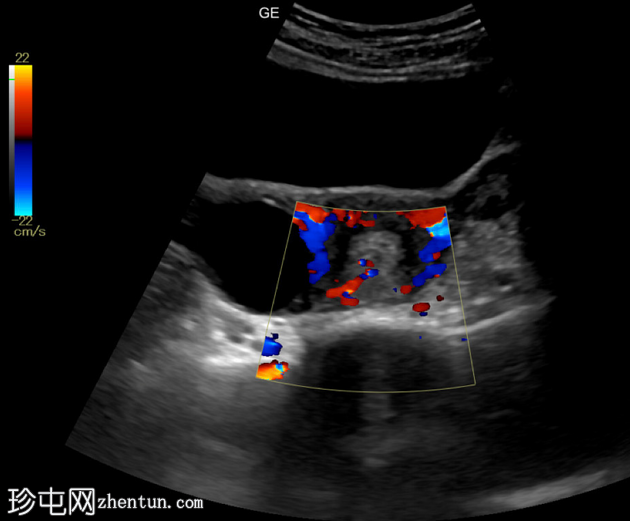

子宫内膜腔内可见边界清晰的高回声病灶,大小为36 x 20 x 21mm,彩色多普勒显示其周围有供血动脉。

子宫内膜腔内可见高回声病灶,并有供血动脉,这是超声检查中子宫内膜息肉的典型特征。患者持续阴道出血一个月。